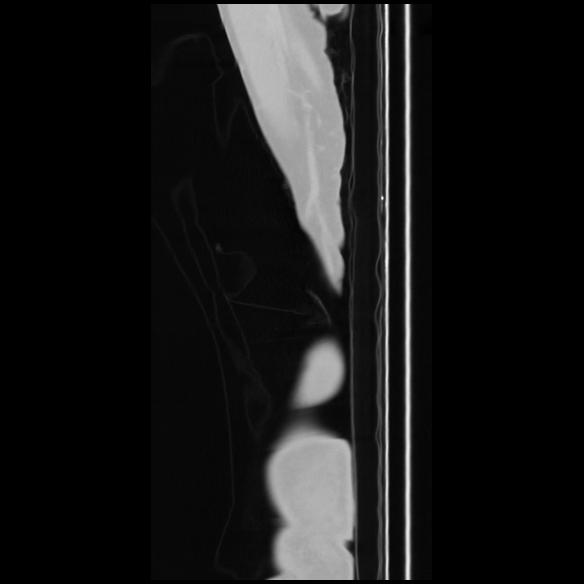

7 CUERPO,CE,Sagittal,3.000,CUERPO,Sagittal,